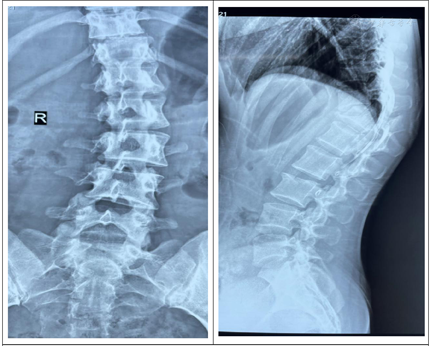

胸椎CT示:胸12椎体骨折伴脱位,相应水平椎管内骨块占位,伴局部后凸畸形。胸椎MRI示:胸12椎体骨折脱位,相应水平硬膜囊及脊髓受压,并脊髓损伤。

西医诊断依据:(1)主诉:坠落伤致双下肢感觉功能障碍1周余。(2)专科检查:抬入病房,被动体位。腰背部可见原手术切口,愈合良好,未见明显红肿及渗出。感觉系统:双下肢感觉大致正常,肛周感觉减退。双下肢体关节位置觉、运动觉存在。运动系统:双侧肢体未见肌肉萎缩。双侧肢体肌张力不高。肌力:左侧:髂腰肌肌力Ⅲ级,股四头肌肌力Ⅲ-级,胫前肌肌力Ⅲ-级,足拇背伸肌肌力级Ⅲ-,趾屈肌肌力Ⅲ-级;右侧:髂腰肌肌力Ⅲ级,股四头肌肌力Ⅲ级,胫前肌肌力Ⅲ级,足拇背伸肌肌力级Ⅲ,趾屈肌肌力Ⅲ级;浅反射:上、中、下腹壁反射正常,肛门反射减弱。深反射:双侧膝腱反射、跟腱反射减弱。病理征:双侧Hoffman征(-),Rossolimo征(-),Babinski征(-),双侧髌阵挛、踝阵挛(-)。骶残留:肛周针刺觉减弱,肛门深压觉减弱,肛门括约肌松弛,自主收缩存在。不可以独自坐立,不能独自站立。洗漱、穿衣、进食等ADL完全依赖。(3)辅助检查:胸腰椎CT(2021年4月29日外院)胸12椎体骨折伴脱位,相应水平椎管内骨块占位,伴局部后凸畸形。胸椎、腰椎、颈椎MRI提示:①胸12椎体骨折脱位,相应水平硬膜囊及脊髓受压,并脊髓损伤;②腰3椎体骨折,胸12附件区软组织肿胀,结合西安市红会医院CT检查胸12附件骨折;③腰5-骶1椎间盘变性、突出,同水平硬膜囊受压;④胸腰骶部软组织水肿;⑤颈椎生理曲度变直,颈3~4、颈4~5、颈5~6椎间盘变性、突出,相应水平硬膜囊受压。